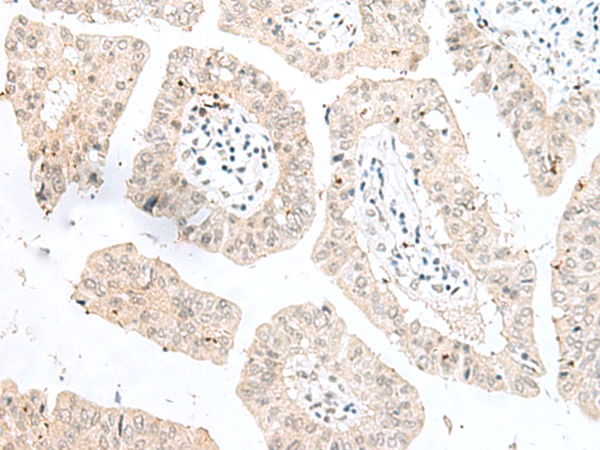

The image is immunohistochemistry of paraffin-embedded Human tonsil tissue using 47316(NGEF Antibody) at dilution 1/35.(Original magnification: 200)

The image is immunohistochemistry of paraffin-embedded Human liver cancer tissue using 47316(NGEF Antibody) at dilution 1/35.(Original magnification: 200)